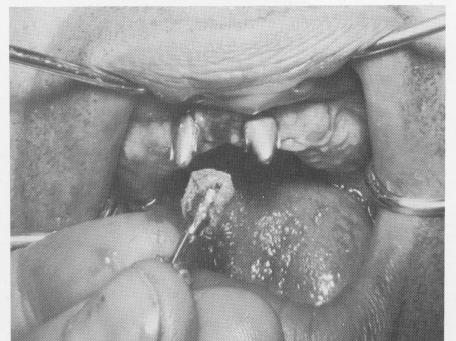

Fig. 4-37. A, The pins were bent flush with palatal bar and B, sealed to it with acrylic.

2 Tripod implant pins bent flush with palatal bar, sealed with acrylic